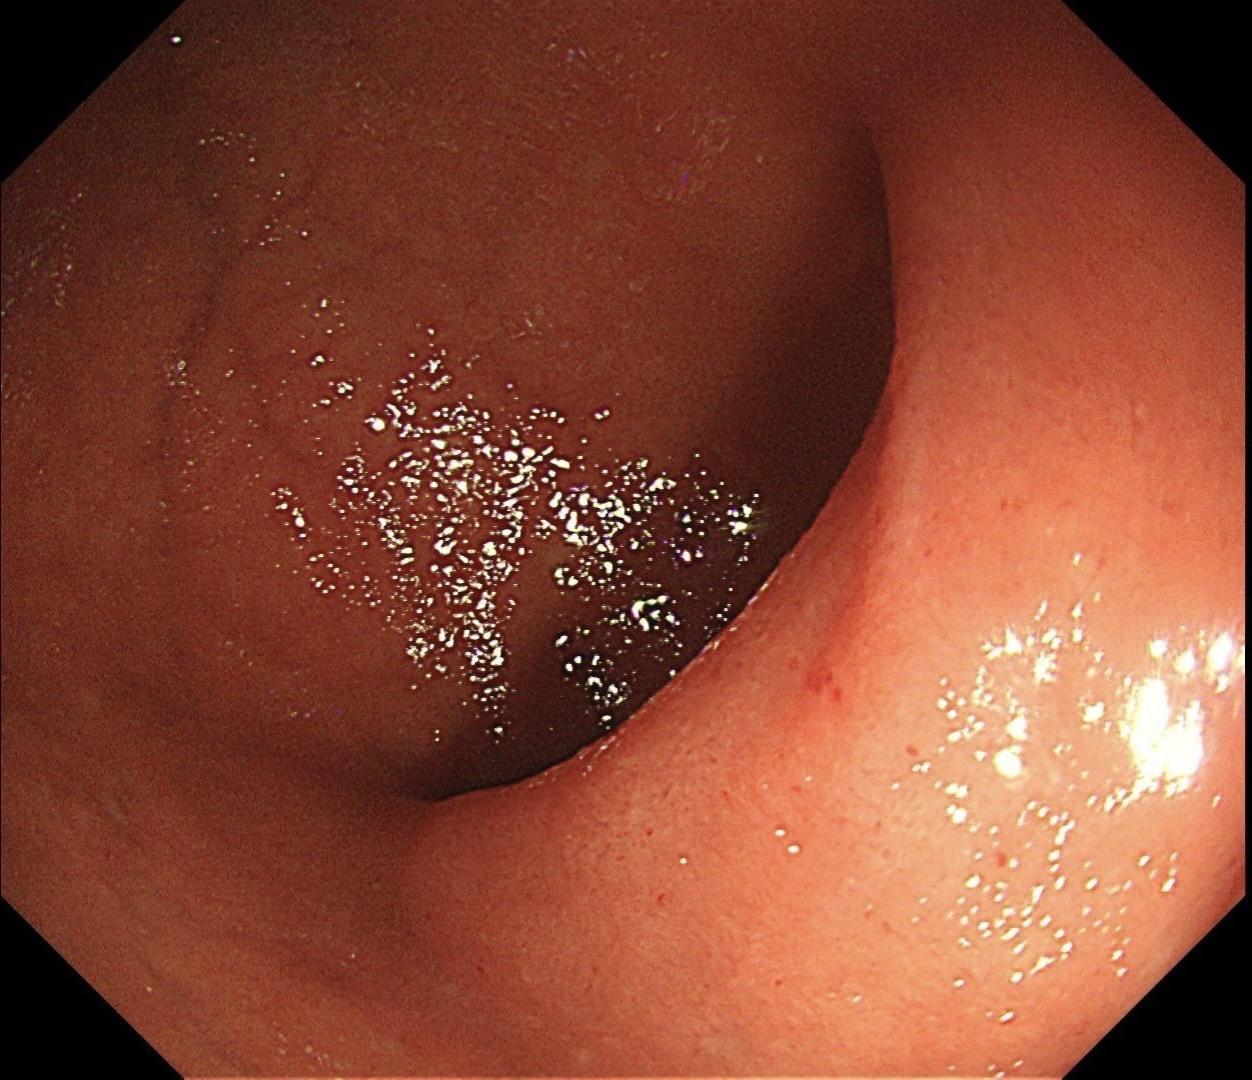

男,40岁,胃双发褪色调病变。慢性胃炎复查,3年前胃镜未见异常,Hp阳性背景,萎缩不明显,胃体下部大弯见一褪色调病变,浅凹陷,5mm左右,换用放大内镜观察,表面结构缺失,血管异型明显,未分化可能性大……胃窦后壁见一白斑,无高度差,NBI浅茶色,放大草草看了下,似有边界,IP增宽,活检待病理……小哥哥胖得几乎没脖子,腹式呼吸太明显~😖